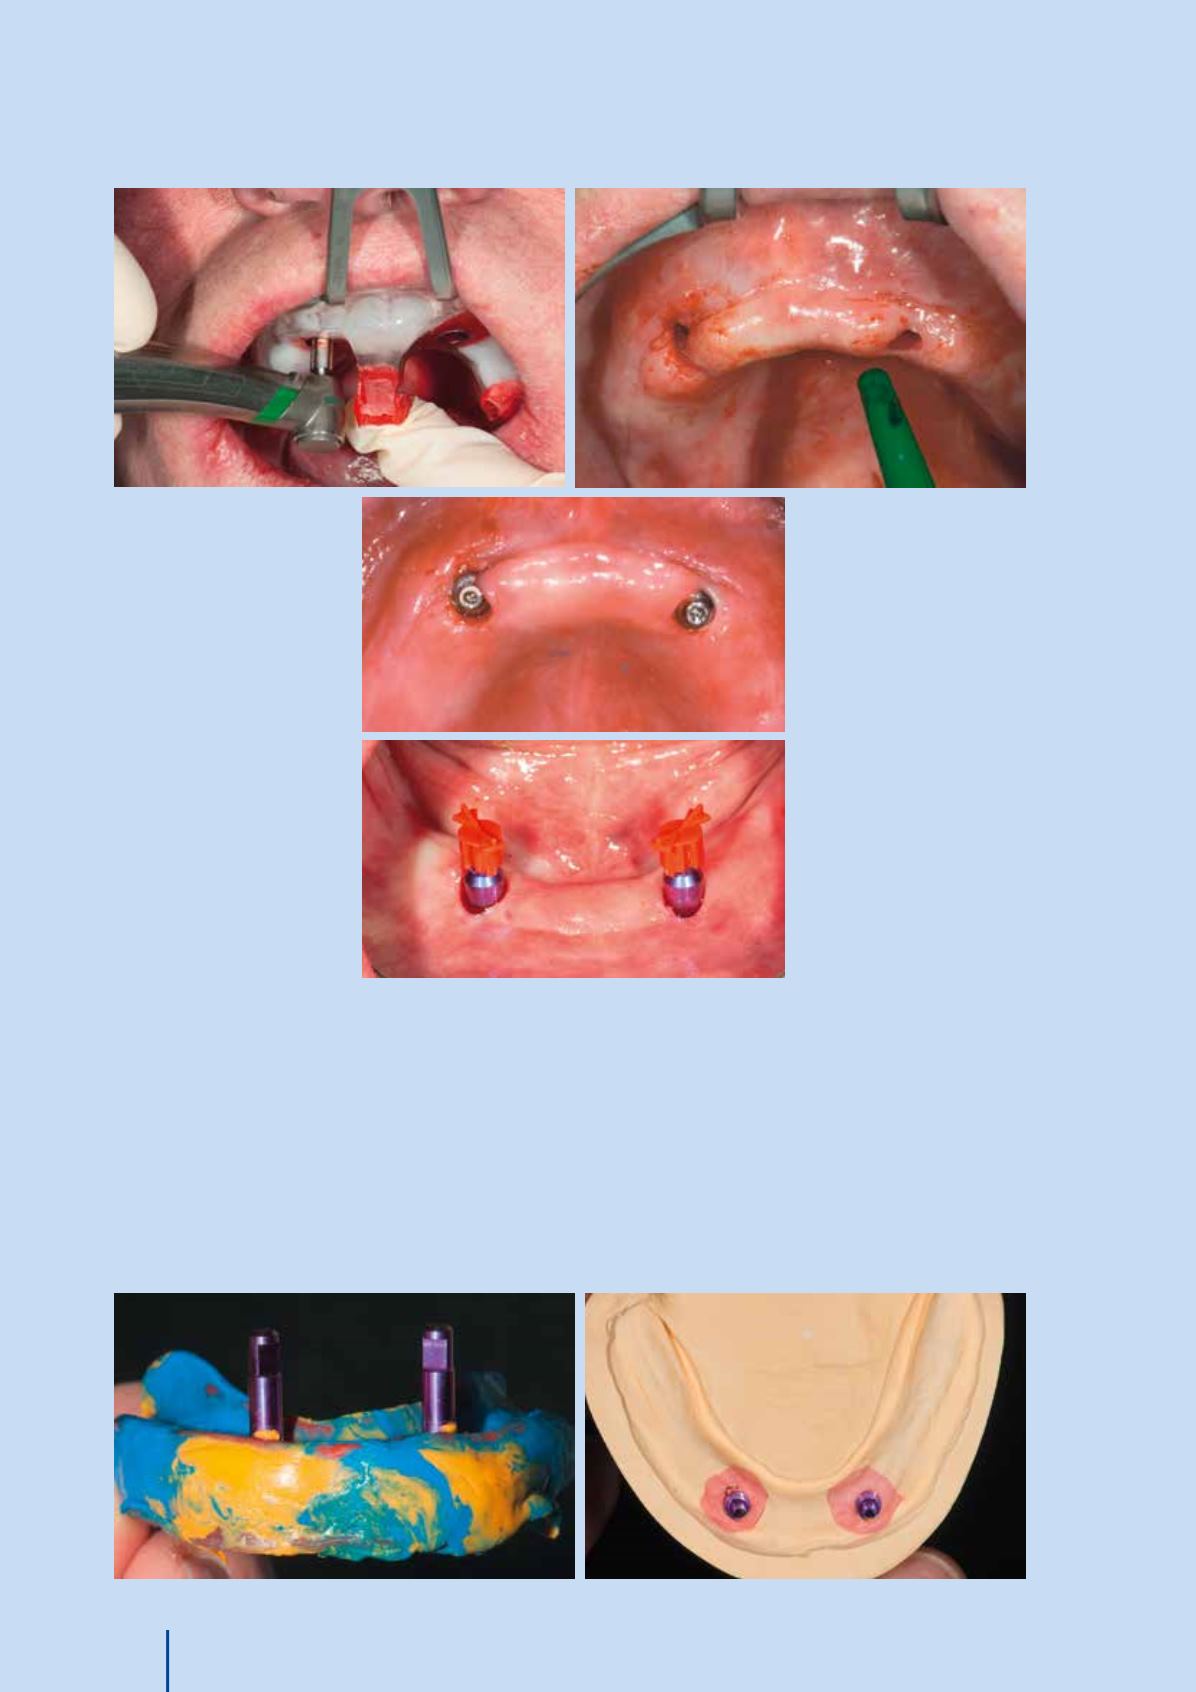

Abb. 35 Die Funktions

überabformung mit den

Laboranalogen

f

Abb. 36

Das Meistermodell

Abb. 31 bis 33

Die Freilegung erfolgte

kieferweise getrennt, wobei

in derselben Sitzung die

Funktionsabformung durch-

geführt wurde, mit gleich-

zeitiger geschlossener

Abformung der Implantate

Abb. 34 Abformpfosten

für die geschlossene

Abformung